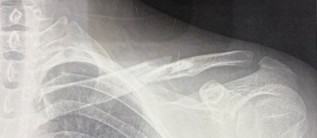

二度目は私,髙橋に起こりました.最終戦である3位決定戦,私はセカンドを担当していたのですが,あまりに不甲斐なく,見かねた𠮷川さんがポジションの交代を提案されました.交代した直後,捕球する際に体勢を崩し左肩から落下.鎖骨を折る重傷を負ってしまいました.日ごろから体を動かしていなかったツケが回りました…

左鎖骨のレントゲン画像